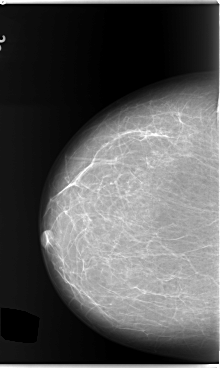

C_0132_1.LEFT_MLO

RIGHT_CC LINES 5888 PIXELS_PER_LINE 3512 BITS_PER_PIXEL 12 RESOLUTION 50 NON_OVERLAY

RIGHT_MLO LINES 5880 PIXELS_PER_LINE 3768 BITS_PER_PIXEL 12 RESOLUTION 50 NON_OVERLAY